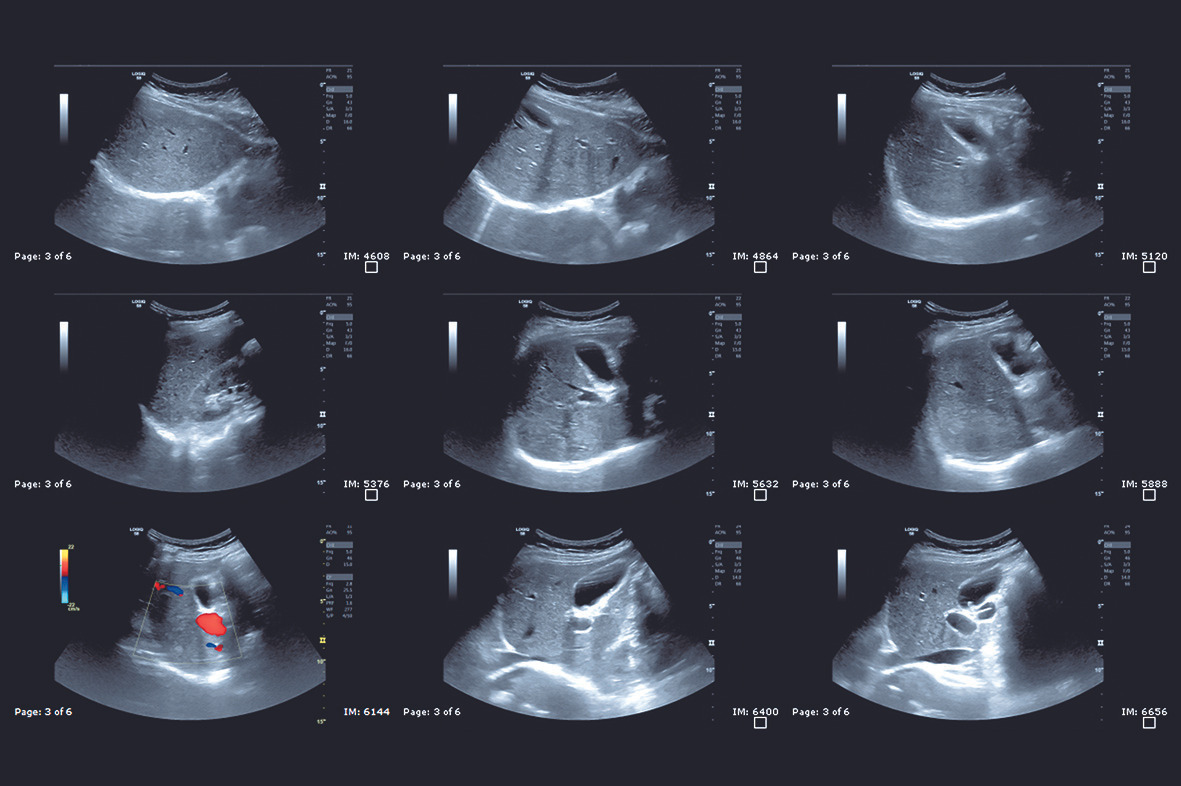

복부 초음파는 초음파(ultrasound)를 이용해 복부 내 장기들의 상태를 확인하는 비침습적 검사 방법입니다. 방사선을 사용하지 않아 인체에 해롭지 않고, 고통 없이 실시간으로 복부 장기들을 관찰할 수 있다는 점에서 가장 기본적이면서도 효과적인 진단도구로 평가받습니다.

초음파 탐촉자(Probe)에서 발생한 고주파 음파가 인체 내부 장기에 부딪혀 반사되며, 복부 초음파로 알 수 있는 것은 바로 이 반사파를 영상화해 간, 담낭, 췌장, 비장, 신장(콩팥), 방광, 대동맥, 림프절 등의 상태를 분석하게 됩니다.

간 질환

- 지방간

- 간경화

- 간암

- 간 낭종

- 간내 혈관 기형